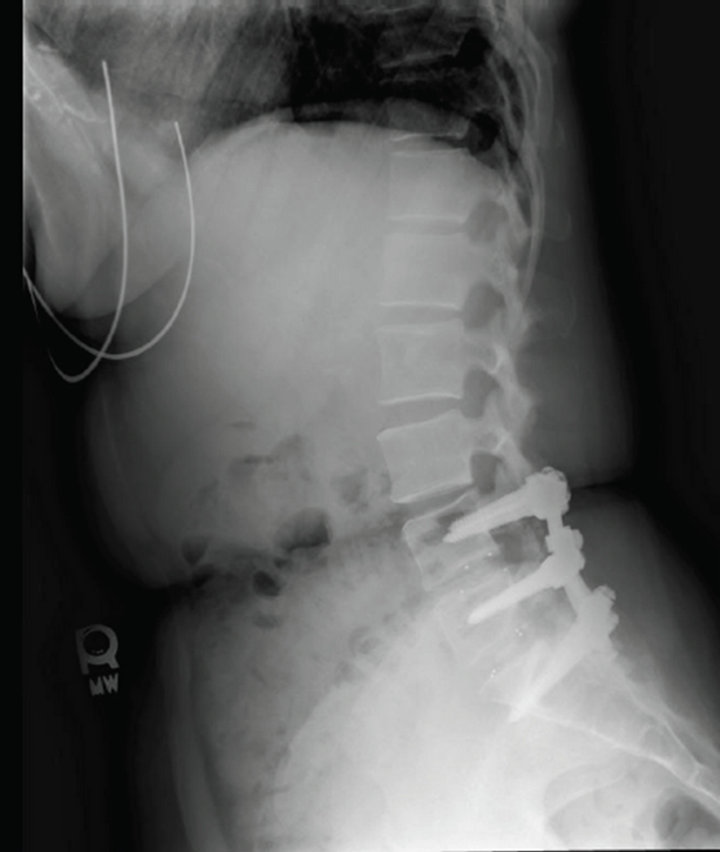

From www.semanticscholar.org

Figure 1 from Fluoroscopically guided epidural blood patch with How Do I Know If I Need A Blood Patch After A Spinal Tap A blood patch may be needed if you have a severe headache after a spinal or epidural. Doctors may look for changes in the fluid that could indicate infection or bleeding, or unusual or uncommon cells that could be a sign of a neurological disorder. After the injection of your blood, the body’s own healing system should take over and. How Do I Know If I Need A Blood Patch After A Spinal Tap.